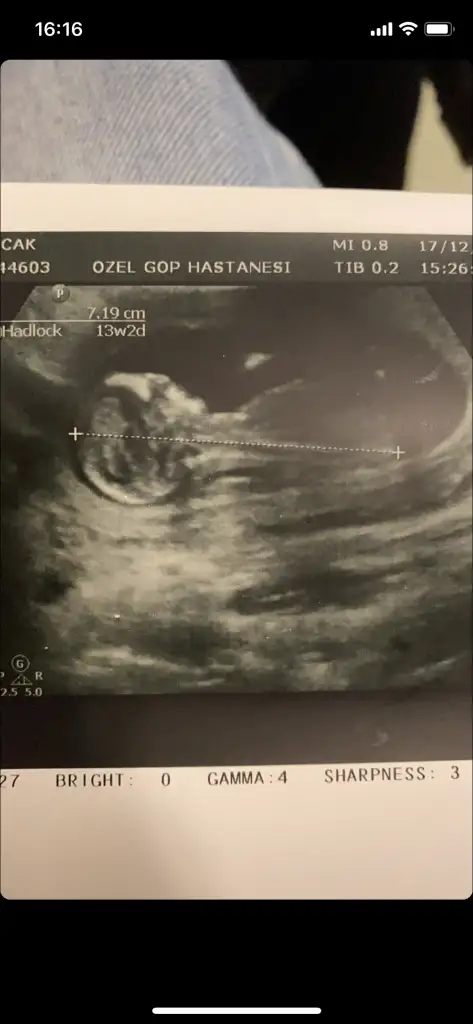

Merhaba Bende geçen hafta dr uma gittim 14 + 3 günlükken. 11 haftalık ikili taramada dr organ görmediğini ama bebğin kız olma ihtimalinin yüksek olduğunu söylemişti. Kendi Kadın Doğum Dr um ise bebek erkek dedi ve ultrason görüntüsü verdi. Ama ben acaba göbek kordonumdudur diyemeden edemiyorum.

Yardımcı olurmusunuz ?

Erkek bebek